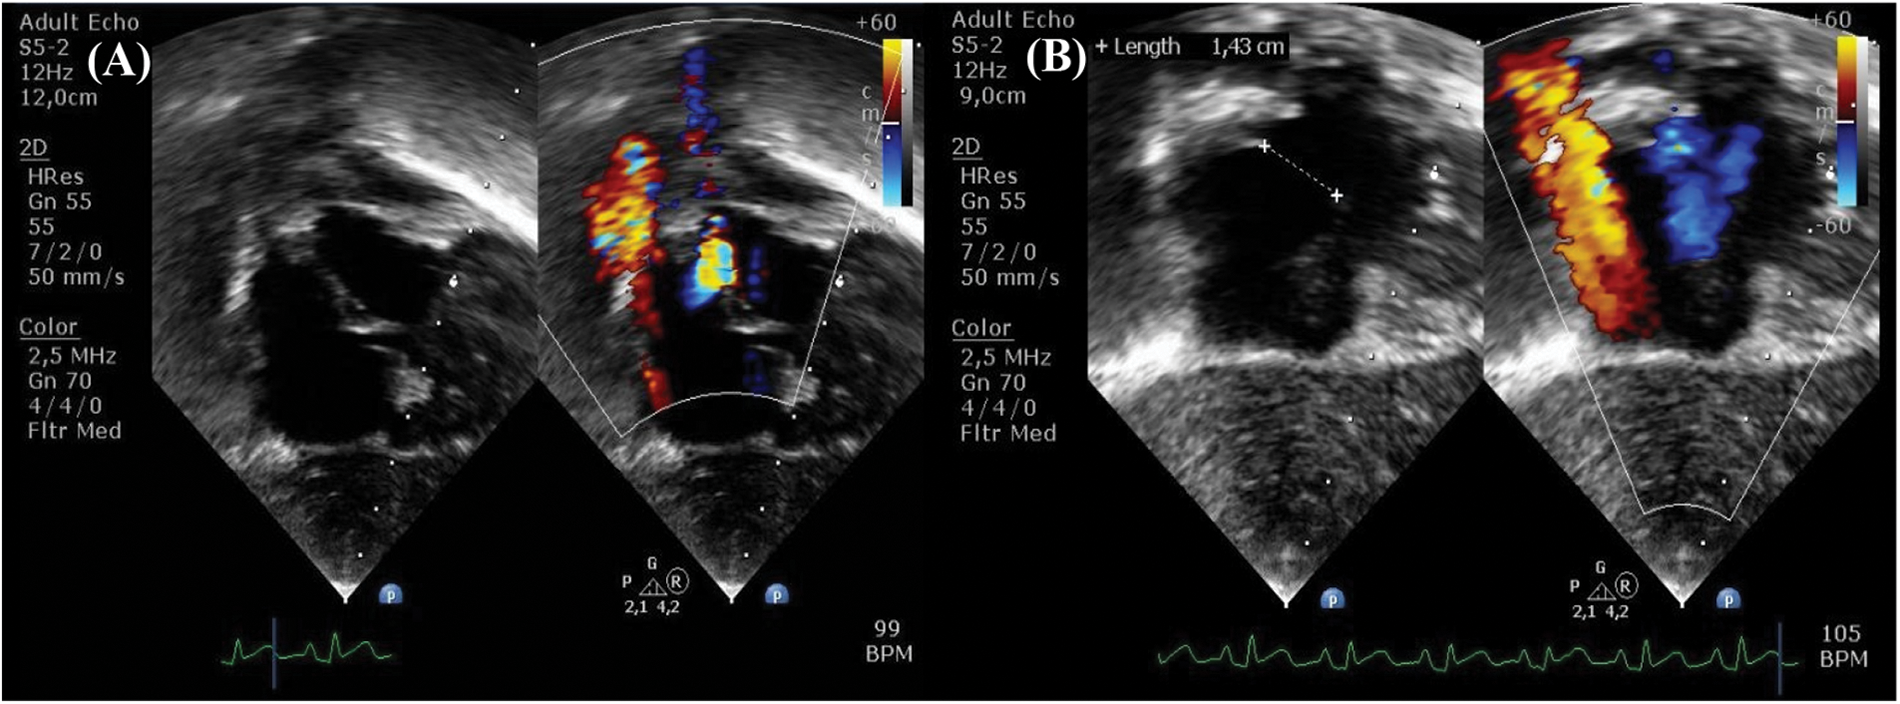

Nitric oxide (NO), as a specific pulmonary artery vasodilator, was immediately given for the patient as the symptoms were suggestive of a pulmonary hypertension crisis. 20 ppm of NO was administered along with a bolus of 500 mL 5% albumin and starting dose of norepinephrine 0.1 mcg/kg/min, resulting in improvement of hemodynamics (BP increased to 92/63 mmHg, CVP reduced to 15 mmHg) and blood gas analysis (pH 7.37, pCO2 33 mmHg, pO2 123 mmHg, SaO2 99%). Gradual weaning of NO therapy was performed until postoperative day (POD) 2, but the patient experienced similar recurrent symptoms. Bedside echocardiography showed a D-shaped left ventricle (LV) and second grade LV diastolic dysfunction [5]. Furthermore, there was right-to-left shunt across the PFO with tricuspid valve gradient of 54 mmHg (Figs. 5A and 5B). No pulmonary regurgitation was observed, and the postoperative right ventricular outflow tract (RVOT) gradient persisted at 16 mmHg. No obstructed flow was seen between the repaired common pulmonary chamber and the left atrium. All these findings confirmed the diagnosis of pulmonary hypertension crisis in a relieved RVOT.

Figure 5: Postoperative day 2 echocardiography in intensive care unit demonstrates (A) left ventricle D-shaped with (B) tricuspid valve gradient 54 mmHg